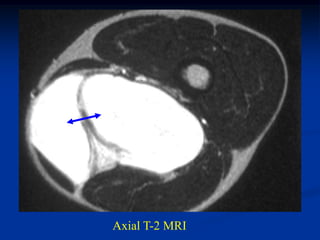

Case #1198.3            CT scan 4/06

09

Sag T-1        Gad

Axial T-1 upper   T-2 upper

T-2 lower         Cor STIR